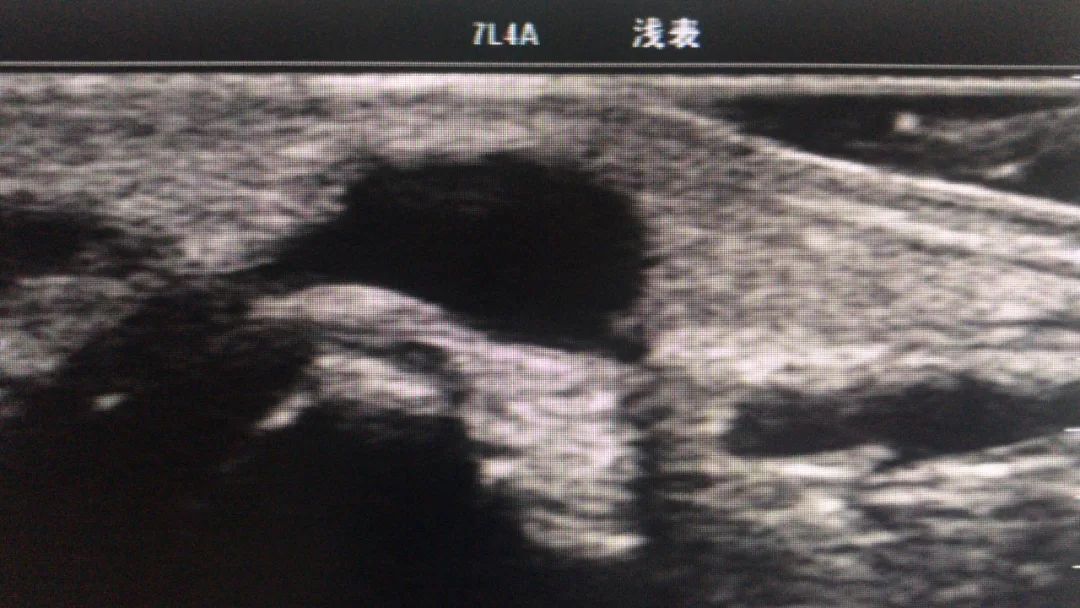

如果囊肿很容易触摸到,通过门诊透照即可方便地鉴别腱鞘囊肿与实体瘤:腱鞘囊肿透照阳性,而实体瘤透照呈阴性。 可采用超声检查帮助诊断腱鞘囊肿。大多数腱鞘囊肿边界清晰、厚壁和回声增强。实性外观的腱鞘囊肿虽然不常见,但可能酷似良性肿瘤。 在隐匿性腕部疼痛患者中,磁共振成像可区分大多数腱鞘囊肿与其他类型的肿块。

左图为手术前,右图为术后半年复发,比原来更大的囊肿